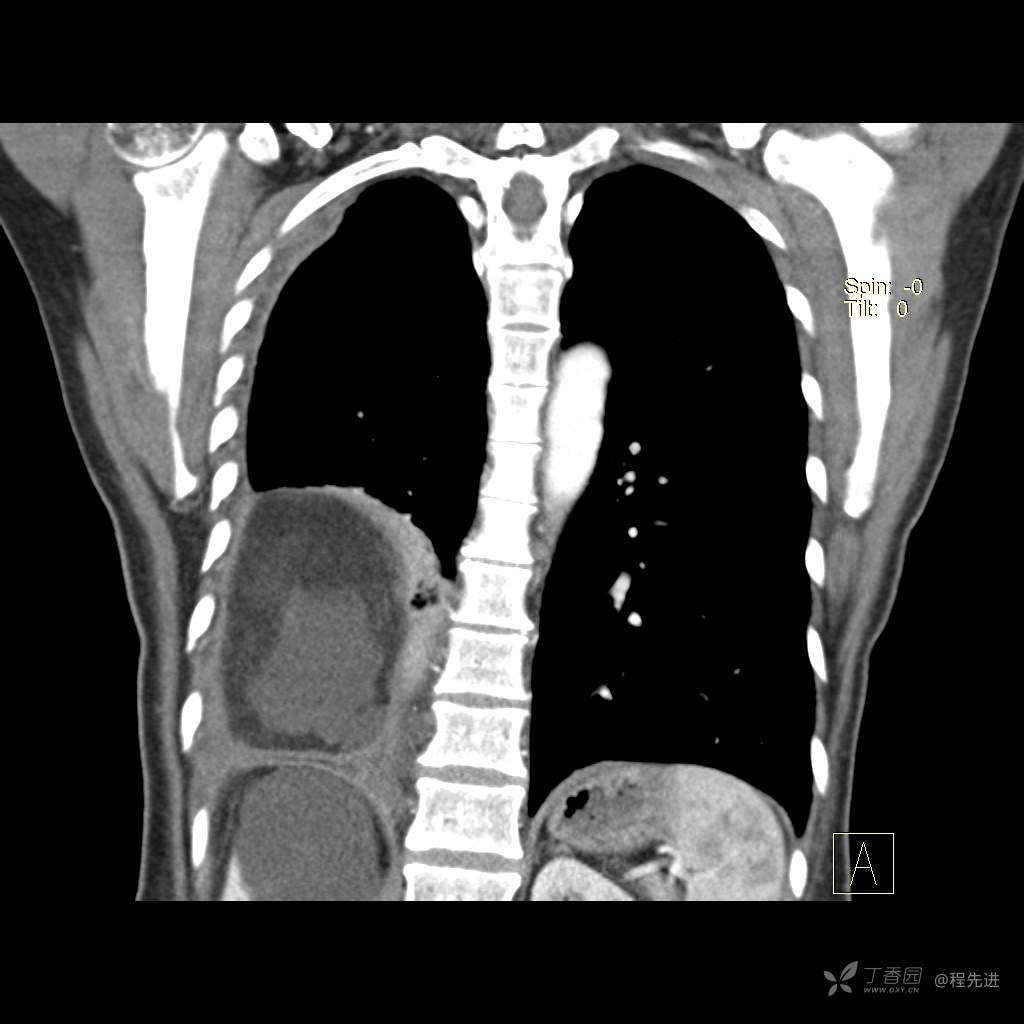

患者性别:女

患者年龄:51岁

简要病史:胸闷半年